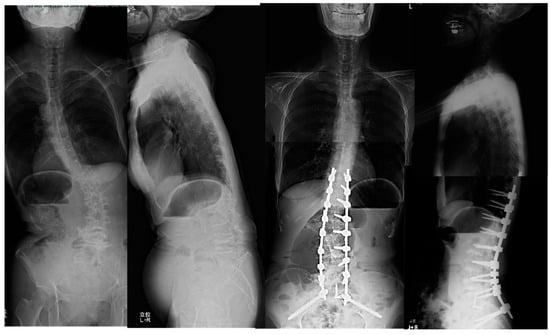

3.1.2. Case 2: 68 Years Old, Female, Adult Scoliosis